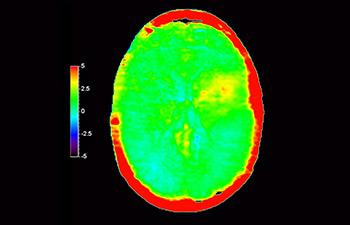

Chemical exchange saturation transfer(CEST)imagingは、MRIにおける分子イメージングの手法であり、その代表的なものにamide protontransfer(APT)imagingがある。MRIはプロトン密度と緩和時間に基づいた画像コントラストを得るのに対し、APT imagingでは可動性タンパク中のペプチド(アミド基)の濃度と交換速度に基づくコントラストが得られ、脳腫瘍の悪性度判定や放射線壊死と脳腫瘍再発との鑑別などに応用されている¹,²。

APTwイメージングでは、アミド基(NH)が対象となる。生体内のアミド基は、主にタンパク質やペプチドに含まれており、平均的には +3.5ppmの周波数に分布するとされる。アミド基のプロトンはバルク水から +3.5ppm離れた周波数帯に存在するため、交換プロトンの信号を抑制させる飽和パルスを +3.5ppmで選択的に照射する。飽和パルスによって信号が抑制されたアミド基のプロトンは、バルク水へ順次移動し、バルク水の信号を低下させる。飽和パルスの周波数を変化させながらバルク水の信号抑制を観察することで、間接的にアミド基を観察することができる(図1)。

CESTは、ごくわずかな共鳴周波数差(数100Hz)にあるプロトンを選択的に飽和させて画像化するため、静磁場B0(数十MHz)のわずかなズレでも、結果に大きな誤差が生じる。APTwイメージングでは、3D DIXON TSEシーケンスを用いB0補正を行っている。本シークエンスの利点は、3 point Dixonによる高精度のB0補正と撮像を一体化させB0不均一性に強い点と、スライスギャップなく3Dで広範囲の撮像が可能となった点である。これにより、B0不均一性に強く安定して広範囲のAPT強調像を撮像することができる⁴。